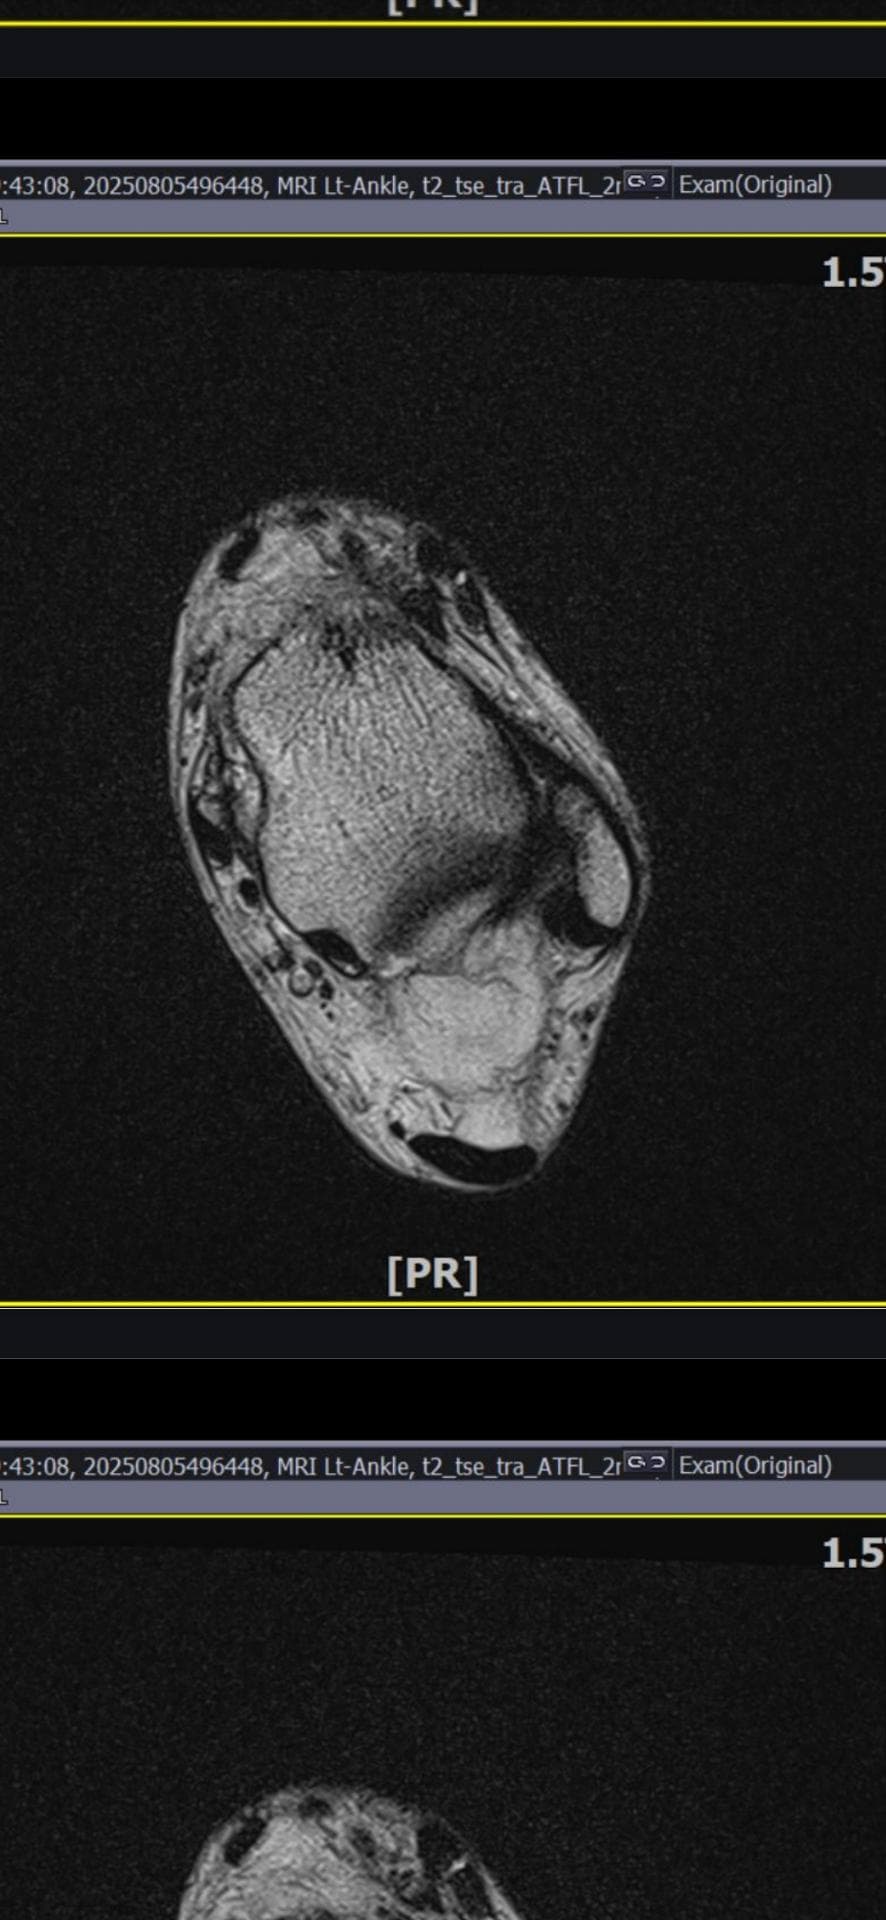

그래도 통증이 남아 8월 5일에 MRI를 촬영했는데, 병원에서는 “인대는 이어져 있고, 이 정도면 재활운동으로 호전될 것”이라는 설명을 들었습니다.

MRI 상 전거비인대와 발목 상태가 정말 회복 단계인지, 아니면 만성으로 넘어가는 건 아닌지 전문가분들의

의견을 듣고 싶습니다.

올려주신 mri를 보면 전거비인대는 연속성이 유지되고 있고 파열이나 큰 손상 흔적은 없어 재활로 회복 가능한 상태로 보입니다 다만 3개월 가까이 활동 시 통증과 미열감이 남아 있는 것은 조직 회복이 아직 완전히 끝나지 않았거나 주변 연부조직 관절 움직임 제한 등으로 인한 과민 반응일 수 있습니다.

초음파와 비교하면 mri 상으로 인대 연속성이 확인되므로 심각한 악화나 재파열은 아닌 것으로 판단됩니다